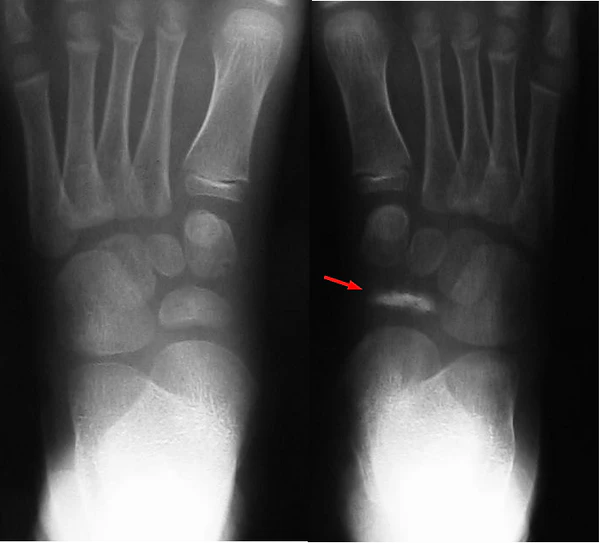

Причина асептического некроза у детей объясняется нарушением процесса окостенения ладьевидной кости. Что подтверждается на рентгенограммах: отмечается сплющивание, фрагментизация ядра окостенения, увеличение межкостного пространства, отделяющего ладьевидную кость от таранной и клиновидной.

Основу диагностики составляют инструментальные методы исследования, рентгенография обеих стоп в прямой и боковой проекциях стоя в опоре дополненная МСКТ и МРТ исследованием пораженной стопы[5].